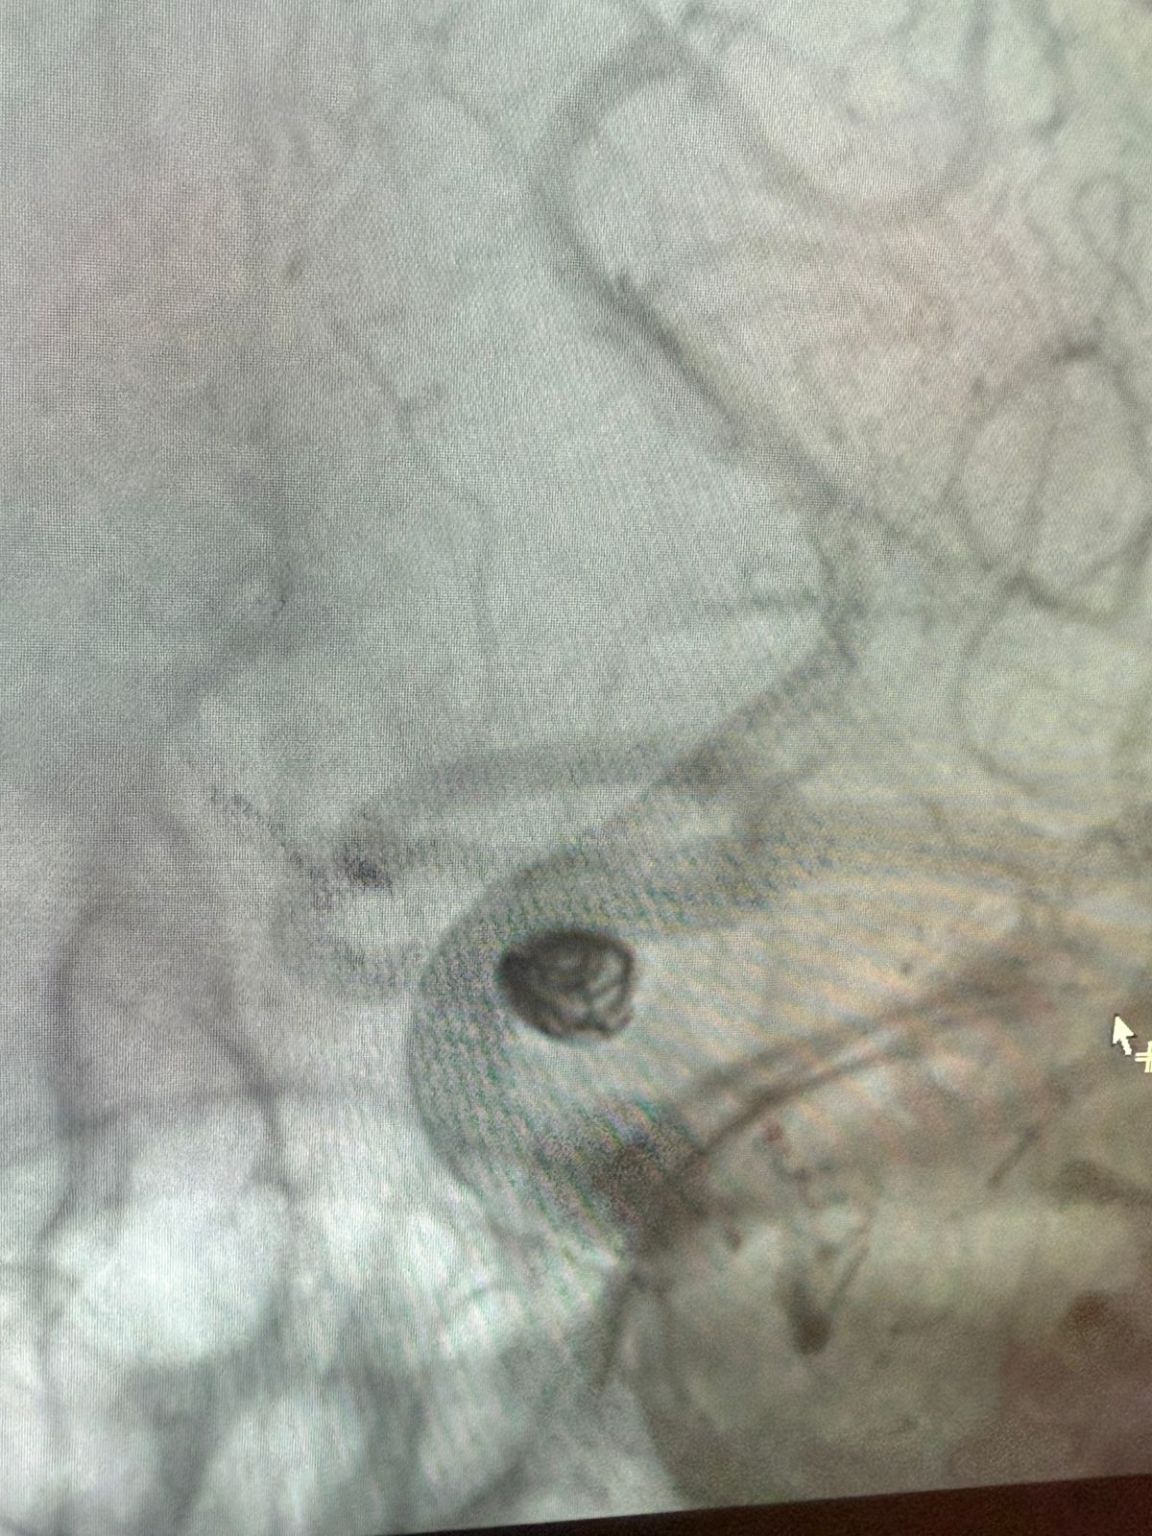

The treatment utilized the Nuva® Flow Diverter (TJED-D 5.0–14), Perdenser® 3D coil, and Frepass® Microcatheter (TJMC18 Plus) for a posterior communicating artery aneurysm.